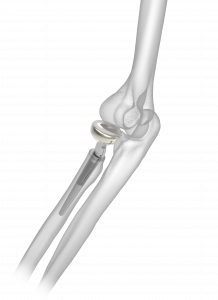

- Anatomic Radial Head Solutions

- Anatomic Radial Head Solutions 2

- Anatomic Radial Head System

- Elbow Plating System

- Radial Head Plating System

- Anatomic Radial Head Solutions

- Anatomic Radial Head Solutions 2

- Anatomic Radial Head System

- Elbow Plating System

- Radial Head Plating System